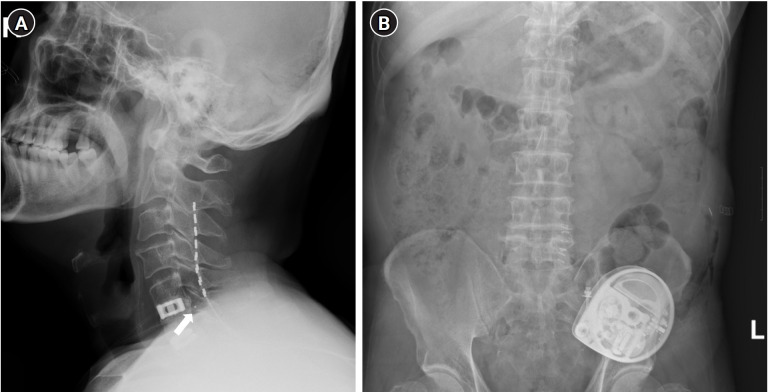

Case: A 64-year-old male patient underwent spinal cord stimulation (SCS) for severe cervical SCI. We proceeded with the ITDD system, placing the catheter tip at the C6 level. After placement of the ITDD system, the patient was monitored for regular refills of morphine sulfate in the drug delivery reservoir every 6 months. We reduced the oral morphine equivalent dose from nearly 333.8 mg/day to 133.8 mg/day.